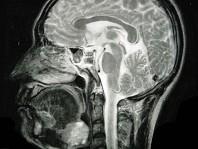

问题 女,40岁,口腔内长一肿块约九个月,逐渐感疼痛,PE:肿块呈淡红色,表面有浅溃疡,CT如图所示,最可能诊断为()

选项 A.舌根癌 B.扁桃体癌 C.扁桃体肥大 D.口底癌 E.腺样体增生

答案 A